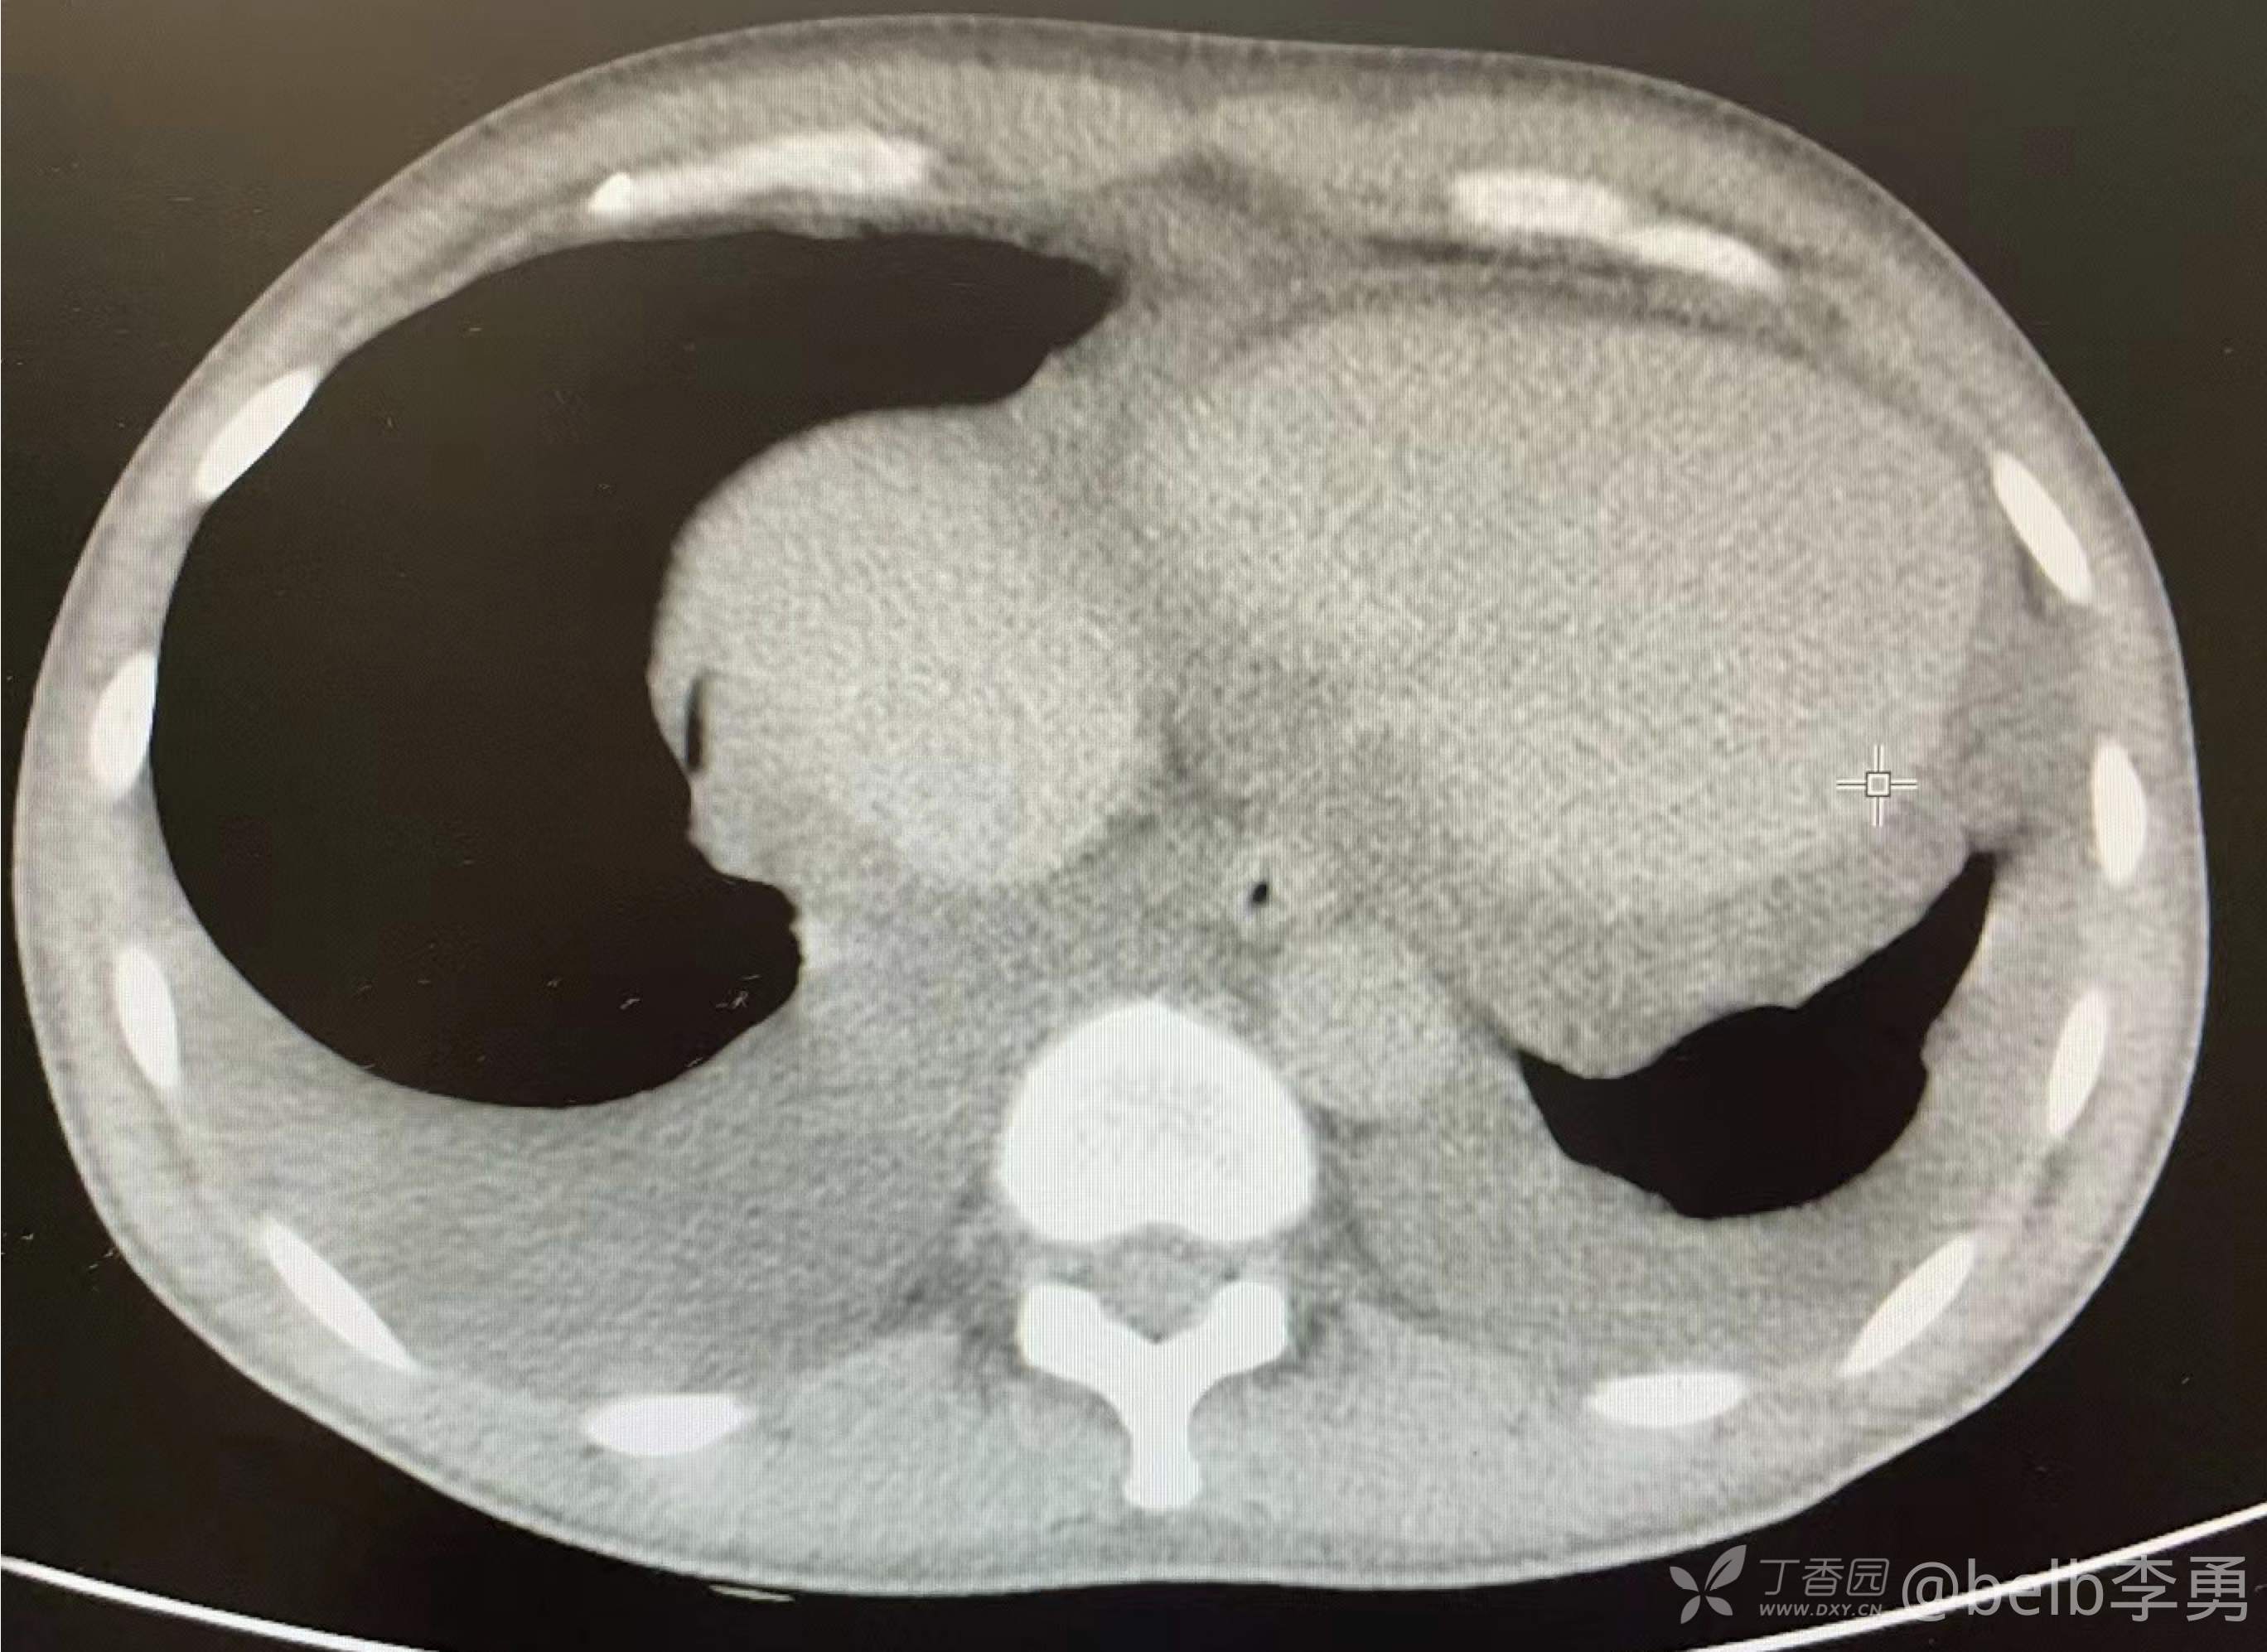

伴心包积液,心影增大。